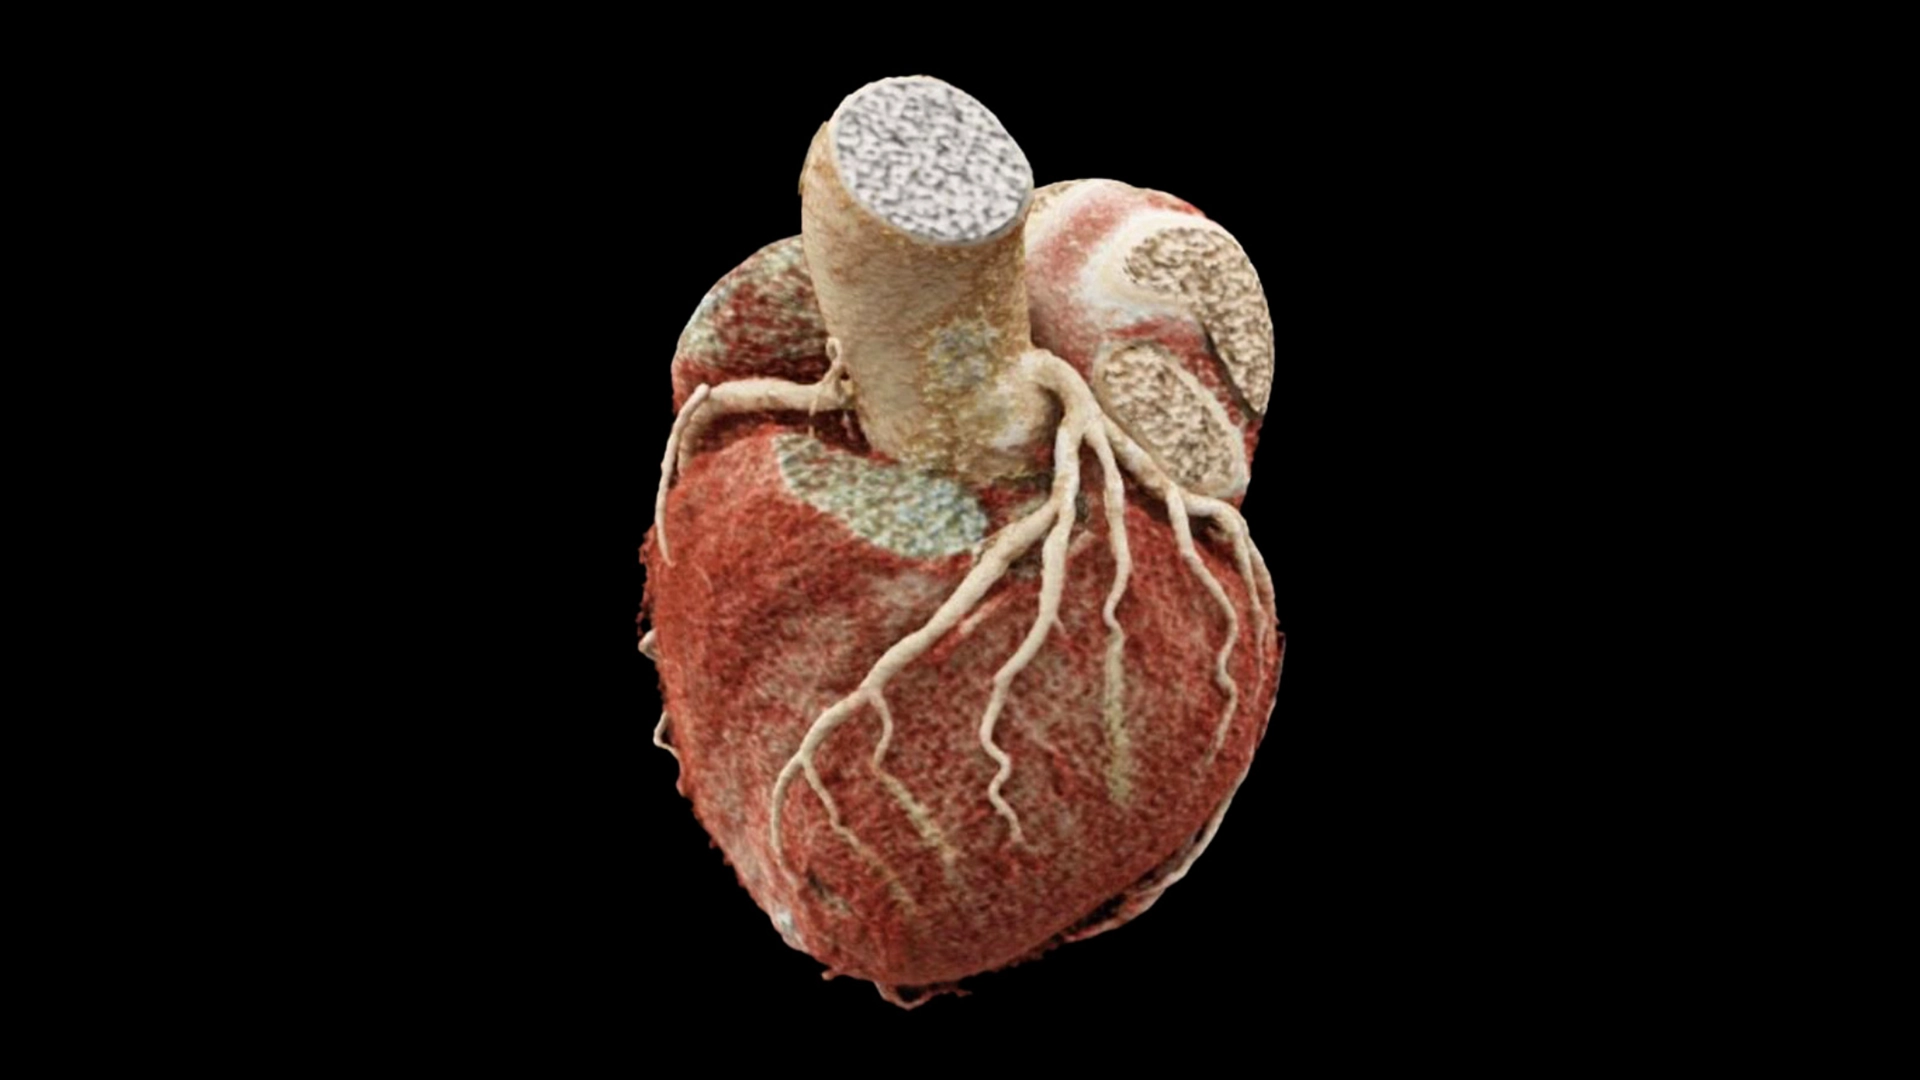

Imaging Highlights

Deliver world-class education in cardiac CT today, and multimodality imaging (MRI, PET, echo) tomorrow.

- Embed AI tools into curricula: coronary plaque analysis, automated CMR, CT-FFR, PCI planning.